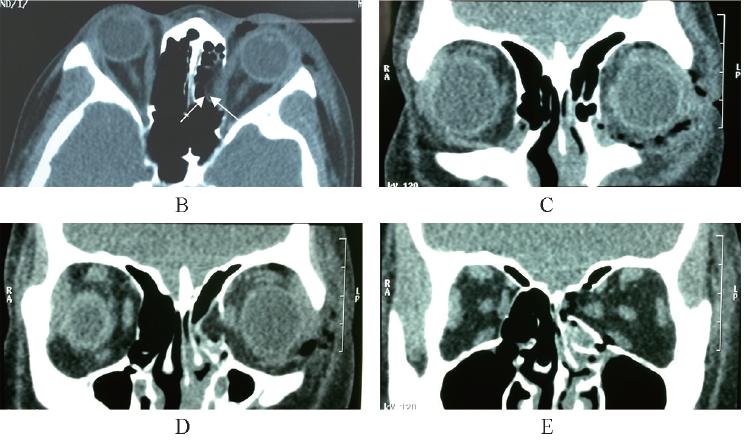

可是在浩瀚的各类CT、MRI学术专著中,介绍我们小眼科的部分永远都是那么一点点,看了半天“砖头书”,实操起来还是没底气。

《眼科CT与MRI学习精要》在身,让行走在江湖的各位小伙伴们不再提心吊胆。

这是我们出品的第6个分册,也是眼科CT与MRI的第2版。